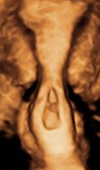

Case Report

Three-Dimensional Ultrasound Assists in Accurately Characterizing Cervical Ectopic Gestation: A Case Report

Cervical ectopic pregnancy (CEP) is rare, and occurs when the blastocyst implants into the endocervical canal. They are particularly dangerous because... Read more